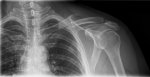

Y en la de ayer,sólo dos semanas después ya no están separados si no incluso se están tocando por más de 5mm que si lo sumamos a los 2 o 3 mm que estaba separado uno del otro el desplazamiento se a reducido en al menos 8mm en tan sólo dos semanas.

Y el triángulo por ese mismo motivo a disminuido bastante

Yo no entiendo mucho…pero creo que era buena señal para evitar la cirugía…

Contando que esos 8mm que ahora ya se ve junto hueso con hueso sea que está pegando que eso no lo sé…